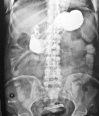

Transmigration and spontaneous passage of a gossypiboma documented on contrast study

Gossypiboma or textiloma is a rare but very unfortunate complication of surgery. It refers to a retained foreign body usually forgotten within the abdominal cavity at the end of an operation. It may be a surgical sponge, gauze pad or other form of textile. We present the case of a middle aged lady who following cholecystectomy had a forgotten gauze which underwent transmural migration and was later expelled via the rectum demonstrated by radiological studies.